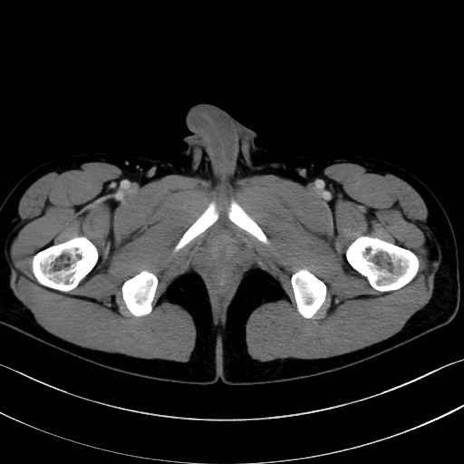

中殿筋(gluteus medius)のCT画像の解剖

中殿筋 (Gluteus medius)